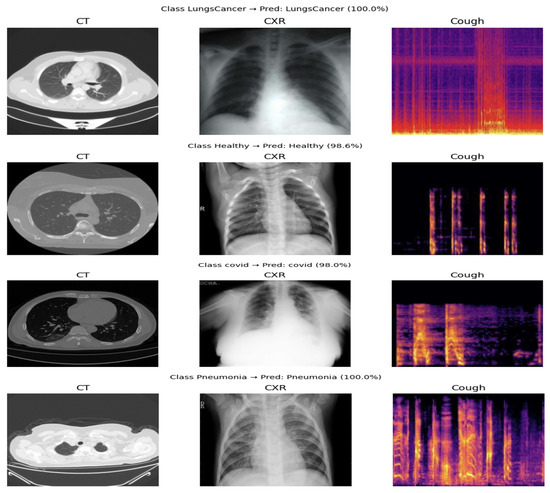

Comparison Between Early and Intermediate Fusion of Multimodal Techniques: Lung Disease Diagnosis

by Ahad Alloqmani and Yoosef B. Abushark

AI 2026, 7(1), 16; https://doi.org/10.3390/ai7010016 - 7 Jan 2026

Early and accurate diagnosis of lung diseases is essential for effective treatment and patient management. Conventional diagnostic models trained on a single data type often miss important clinical information. This study explored a multimodal deep learning framework that integrates cough sounds, chest radiograph [...] Read more.

Early and accurate diagnosis of lung diseases is essential for effective treatment and patient management. Conventional diagnostic models trained on a single data type often miss important clinical information. This study explored a multimodal deep learning framework that integrates cough sounds, chest radiograph (X-rays), and computed tomography (CT) scans to enhance disease classification performance. Two fusion strategies, early and intermediate fusion, were implemented and evaluated against three single-modality baselines. The dataset was collected from different sources. Each dataset underwent preprocessing steps, including noise removal, grayscale conversion, image cropping, and class balancing, to ensure data quality. Convolutional neural network (CNN) and Extreme Inception (Xception) architectures were used for feature extraction and classification. The results show that multimodal learning achieves superior performance compared with single models. The intermediate fusion model achieved 98% accuracy, while the early fusion model reached 97%. In contrast, single CXR and CT models achieved 94%, and the cough sound model achieved 79%. These results confirm that multimodal integration, particularly intermediate fusion, offers a more reliable framework for automated lung disease diagnosis. Full article